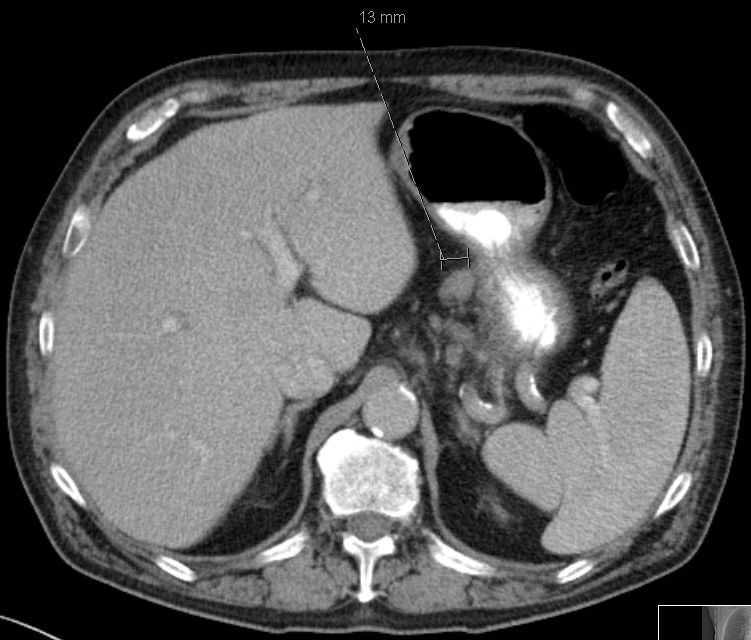

| Magenantrum | 1-jährige Frau mit fortgeschrittenem Magenantrumkarzinom![]() |

![]() | ||